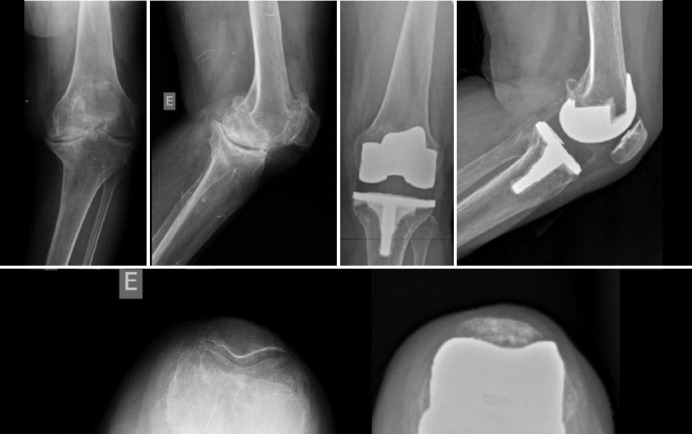

Objective: The objective of the article was to do a comparative study between Smith & Nephew ® prosthesis with constricted polyethylene against the standard in patients submitted to total knee arthroplasty surgery during a short-term follow-up. The aim was to analyze the survival of the related implants due to the range of movement and radiographic aspect.

Methods: The sample was divided into two different groups: constricted polyethylene and standard polyethylene. A clinical analysis of the patients was carried out, and it was verified whether implant loosening had occurred.

Results: This study evaluated 61 patients in a period of 2 years, 29 in the constricted polyethylene group. The pre-operative deformities were predominantly considered severe. In the postoperative, the tibial-femoral angle varied on average between 5 - 6° of valgus. The total range of movement in the post-operative was above 101° in both groups. One loosened implant in the constricted polyethylene group was observed.

Conclusion: The patients treated with constricted polyethylene had the same range of movement as the control group. There was no significant difference between both groups related to loosened implants in short-term follow-up. Level of evidence III; Retrospective study.